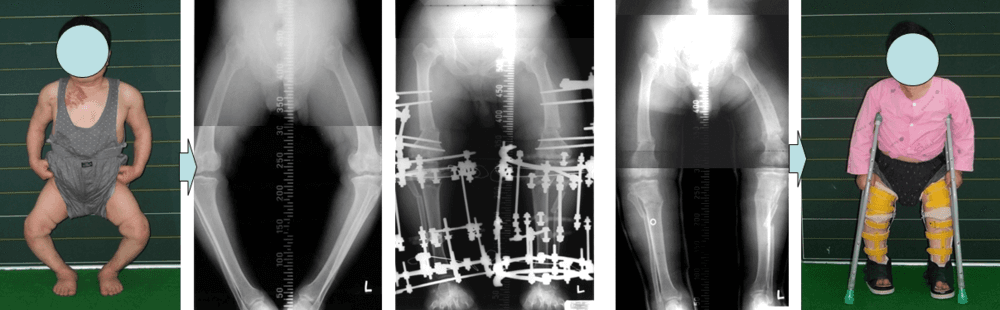

왼쪽다리에 변형이 온 소아마비 환자의 하지 교정술

소아마비환자의 하지변형에 대한 교정